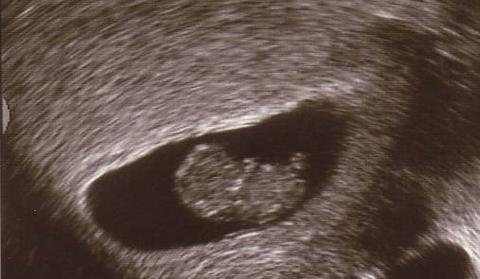

Записвам се малко плахо в новата тема, тъй като все още не съм посещавала гинеколог след като миналата седмица разбрах, че съм бременна. След 4 години опити за пръв път видях заветните 2 чертички, освен това имам и два положителни кръвни теста. Според посочения в темичката калкулатор терминът ми е на 09.07.2022, а според този в телефона ми 07.07.2022 г.